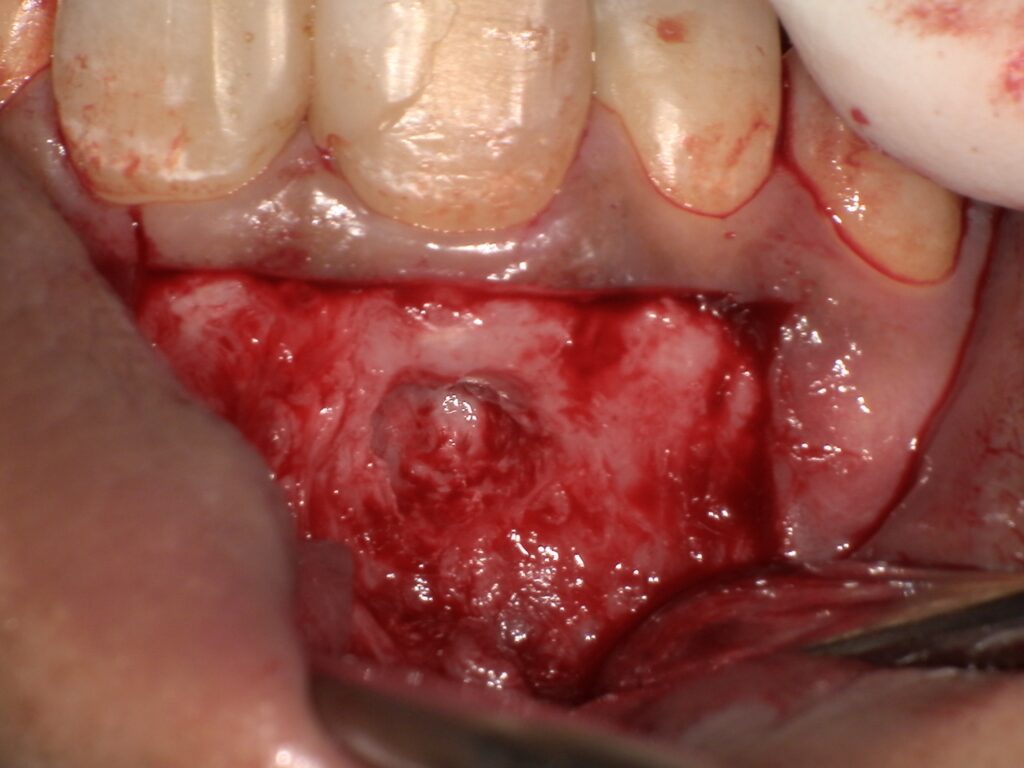

ラバーダム防湿とは? みなさん「ラバーダム防湿」という処置をご存知ですか?ラバーダム防湿とは、根管治療や詰め物の治療をする際に唾液が入るのを防いだり、器具の誤飲を防ぐ為に行うゴム製のマスクのようなものです。 主に根管治療の時に使用されますが、根管治療をしたことがある方でも「ラバーダム防湿はしたことがない」という方が多いかもしれません。ラバーダム防湿を行うことで、より安全で精度の高い治療を行うことができます。 なぜラバーダム防湿を行うのか ラバーダム防湿を行うと時間やコストがかかります。それでも行った方がいいメリットをお話しします。 唾液や細菌の侵入を防ぐため お口の中にはたくさんの細菌が存在しており、細菌を含む唾液が根管内に入り込むと感染を広げたり、再感染の原因になる可能性があります。ラバーダム防湿を行うことで唾液が侵入するのを防ぎ、治療の成功率を高めます。 器具の誤飲を防ぐため 治療にはたくさんの器具を使用します。その中にとても小さな器具もあるため、お口の中に落ちてしまうと誤飲の可能性があります。 ラバーダム防湿を行うことで、万が一器具を落としてしまっても受け止められるので器具の誤飲を防げます。 こちらは、根管治療中のラバーダム防湿です。 お口の中の粘膜を保護するため 根管治療では薬剤を使用します。その薬剤が舌や粘膜に触れると火傷してしまう恐れがあるため、ラバーダム防湿を行い薬剤が漏れてしまうのを防ぎます。 乾燥した状態で治療するため 詰め物や被せ物を合着させる際は、歯を十分に乾燥させる必要があります。その際に、唾液や吐いた息によって歯が湿ってしまうと詰め物等がすぐに外れてしまう可能性があります。 ラバーダム防湿を行うことでしっかりと防湿ができるため、歯を湿気から守り詰め物や被せ物を合着することができます。 治療の精度が上がる ラバーダム防湿を行うことにより、視野が広がり唾液も入らないので、より正確で丁寧に治療が行えます。 患者さんの負担軽減 メリット 水や削った粉がお口の奥に流れにくくなるため、むせにくくなる 薬剤が舌や粘膜に触れるのを防ぎ、火傷のリスクを軽減できる 唾液や細菌の侵入を防ぐため、治療の成功率が上がる 治療を受けやすくなる デメリット ラバーダムの設置に時間とコストがかかる 口が乾燥する、息苦しさを感じることがある 導入している歯科医院が少ない このようにラバーダム防湿は、患者さんにとっても術者にとっても、より安全で精度の高い治療を行うために大切な処置のひとつです。 当院では保険診療でもラバーダム防湿を行っております。気になることがございましたら、ぜひお気軽にお声掛けください。 歯科医師 安達